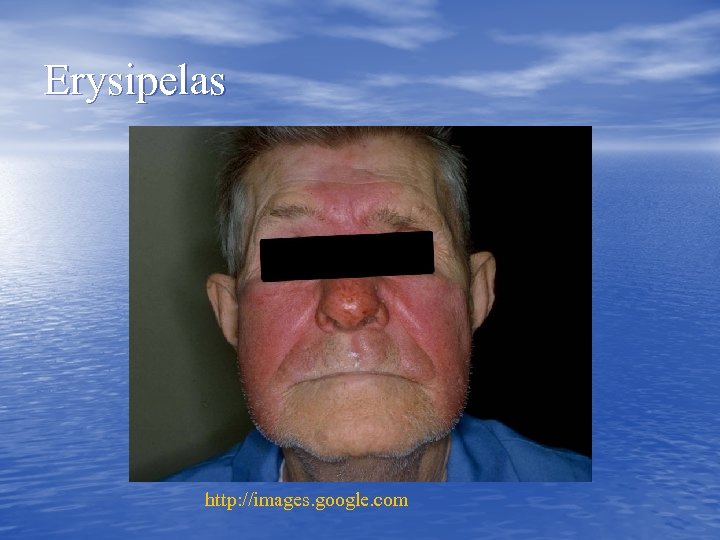

Erysipelas http: //images. google. com

Erysipelas http: //images. google. com